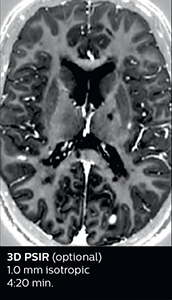

The abbreviated MS protocol for brain is only around 9 minutes, so in case of suspected multiple sclerosis, one or two more advanced sequences may be added, such as PSIR (phase sensitive inversion recovery) or susceptibility-weighted sequences to help us make more confident diagnoses in these inflammatory cases.

In this example, the optional 3D multishot susceptibility weighted sequence with 0.6 mm isotropic voxels is 2 lesions with a central vein sign (arrows) and one lesion with a phase-rim sign (arrowhead). The total scan time, including SmartBrain and axial PD/T2 3mm, is 11:10 min. and is 18:30 min. with the optional 3D PSIR and 3D SWI multishot included.

“We used to have long examination times for certain types of patients, a few lasting more than 40 minutes,” says Dr. Savatovsky. “What is remarkable, is that now all these examinations are below 30 minutes, which opens up opportunity to add more sequences when needed. It’s really hard to keep a patient for more than 40 minutes in the scanner, but because we have now cut scan times by at least 10 minutes, we can add more sequences without making the exam too long. And this is where the new system helps us make a difference. Examples include our examinations for informing brain tumor classification or giant cell arteritis workup, or for intracranial wall imaging – so in patients where we need several advanced sequences or high resolution sequences.” “We added three additional sequences in our brain neoplasm classification exam: a 3D SWI sequence, APT and ASL on top of 3D morphologic sequences, an isotropic DSC (dynamic susceptibility contrast) and multivoxel spectroscopy. I think that in patients that need a classification for brain mass, for example, we can provide a more detailed and confident diagnosis than before, allowing the clinicians to decide for either a medical workup if no tumor is suspected, or for neurosurgery as soon as possible if a neoplasm is suspected.” “In multiple sclerosis patients, we increasingly include a multishot susceptibility sequence [3] in our routine cases, thanks to the shorter scan times. Our abbreviated MS protocol for brain is around 8 to 9 minutes, so we can ask for one or two additional sequences to visualize the central veins, or to get an additional contrast to better depict posterior fossa lesions. In cases of white matter lesions of unknown significance on FLAIR images, for example when we see high signal hyperintensities in the brain, we can add on more advanced sequences such as PSIR (phase sensitive inversion recovery) or susceptibility-weighted sequences to help us in distinguishing between MS and nonspecific or vascular abnormalities in these inflammatory cases.”